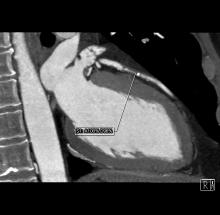

IMRIS Inc. announced that Visius iCT, its ceiling-mounted intraoperative computed tomography scanner, has received Health Canada licensing allowing for sales and marketing in the country.